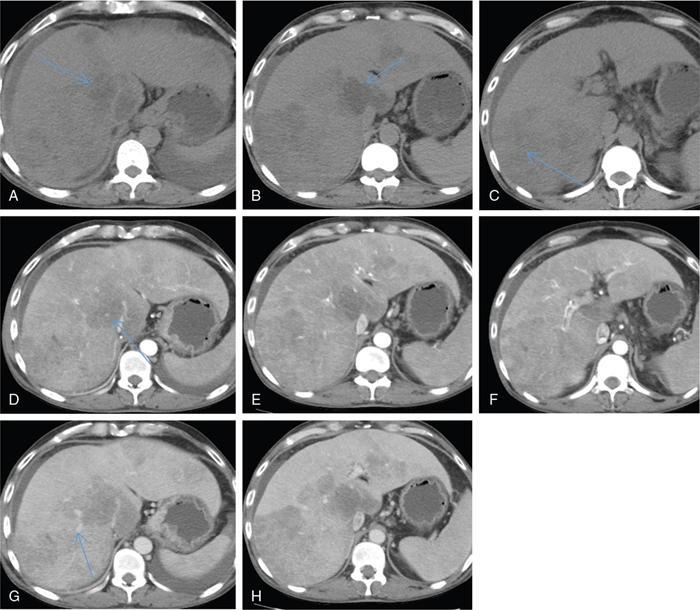

Excessive triglyceride accumulation within hepatocytes is defined as hepatic steatosis. Major conditions associated with hepatic steatosis include alcoholic fatty liver disease (AFLD) and nonalcoholic fatty liver disease (NAFLD). Causes of hepatic steatosis are discussed in Table 9.10.3. NAFLD is the most common form of hepatic steatosis and discussed in detail below. Up to 90% of patients with chronic alcoholic intake have fatty liver. Those with pure AFLD have a 10% risk of progressing to cirrhosis. Consumption of 30 g ethanol/day shows increased risk of chronic liver disease and cirrhosis. Other risk factors include female sex, obesity, cigarette smoking, obesity and associated risk factors. These factors are divided into 2 main categories which can cause fatty liver: inborn errors of metabolism and acquired metabolic disorders. Inborn errors of metabolism include abetalipoproteinemia, galactosemia, glycogen storage disease, hereditary fructose intolerance, homocystinuria and Wilson disease. Inflammatory bowel disease, jejunoileal bypass, malnutrition, starvation and total parenteral nutrition are acquired metabolic factors associated with increased risk. Chronic HCV infection, is associated with hepatic steatosis, with prevalence of 40%–80%. Hepatic steatosis can be seen as an adverse reaction to some medications such as tetracycline, valproic acid, some of chemotherapeutic agents, dexamethasone, amiodarone, methotrexate, tamoxifen and acetylsalicylic acid. Either microvesicular or macrovesicular steatosis can be observed in drug-induced hepatic steatosis. It generally occurs with therapy lasting several weeks or months and is reversible after discontinuation. The leading cause of hepatic steatosis in paediatric population is NAFLD. Six per cent of these patients develop cirrhosis and end-stage disease. Other less common causes include starvation and malnutrition, drugs (glucocorticoids, oestrogens, tetracyclines, and methotrexate), intoxications (carbon tetrachloride, organic phosphates, organic solvents, and alcohol), metabolic disorders, hepatitis C infection, and total parenteral nutrition. NAFLD is defined as steatosis affecting >5% of hepatocytes in the absence of a secondary cause. NAFLD represents a spectrum of disease, ranging from simple steatosis to steatohepatitis through to fibrosis and cirrhosis and in some cases hepatocellular carcinoma. NAFLD is a growing epidemic worldwide in part due to obesity and insulin resistance leading to liver accumulation of triglycerides and free fatty acids. Nonalcoholic steatohepatitis (NASH) is defined by histologic terms as a necroinflammatory process whereby the liver cells become injured in a background of steatosis. 20% of patients with NAFL progress to NASH, which progresses to fibrosis and cirrhosis over a 15-year time period (Fig. 9.10.3). The definition of NAFLD requires imaging or histology evidence of steatosis and no causes for secondary hepatic fat accumulation like significant alcohol intake, drugs or hereditary disorders (Table 9.10.4). The incidence of NAFLD ranges from 20% to 30% in Western countries and 5%–18% in Asia. As it currently stands, NAFLD represents the second most common reason to be listed for a liver transplant. The prevalence of NAFLD is higher in patients with obesity, diabetes, and patients with hyperlipidaemia. Prevalence increase with age from less than 20% at age 20 to more than 40% over 60 years of age. Males show a higher risk for progression to NASH and fibrosis (Table 9.10.5). Up to 90% of patients with NAFLD have simple steatosis, and about 30% of patients with NAFL develop NASH, and in again about 30%–40% of NASH patients the disease progresses to manifest fibrosis and cirrhosis NAFLD related cirrhosis has a 10-year mortality of 25% and a 5% chance of developing end-stage liver disease and HCC. The theory implicated in the pathogenesis of NAFLD is the two-hit theory. Insulin resistance, enhanced dietary influx and increased hepatic lipogenesis leading to accumulation of triglycerides (TG) and FFA in the hepatocytes is the first hit. The lipid peroxidation, mitochondrial dysfunction and inflammation resulting in hepatocyte damage and development of liver fibrosis is the second hit. The stages of NAFLD on histology range from steatosis initially to hepatic fibrosis in late stages. In the steatotic stage large (macro-) and small (micro-) vesicles of fat, predominately triglycerides, accumulate within hepatocytes. The affected parenchyma is divided into thirds: 5%–33%, 34%–66% and >66% and graded as mild, moderate and respectively. Ballooned hepatocytes with accompanied steatosis and inflammation are characteristic of the steatohepatitis stage. Fibrosis has a characteristic appearance with early lesions showing a perisinusoidal deposition followed by periportal fibrosis which progresses to bridging. Raised GGT is the most common liver enzyme elevated in NAFLD. Transaminases are within normal range in 80% patients. No specific blood tests can diagnose NAFLD. Liver biopsy has remained the gold standard for diagnosis and quantification of liver fat. Drawbacks, however, include invasive nature, sampling error and procedure related complications like bleeding. Various imaging techniques are currently available in diagnosing and quantifying liver fat. MRI in particular proton density imaging and MR Spectroscopy have revolutionized imaging of fatty liver. Normal liver parenchyma is the same as or slightly more echogenic than the adjacent kidney and spleen. Fat deposition leads to increased echogenicity of liver. Decreased beam attenuation in patients with fatty change leads to poor visualization of structures such as intrahepatic vessels, bile ducts and liver lesions and in severe cases diaphragm (Table 9.10.6). Fatty liver can be graded on USG as: US has a fair accuracy of detecting the moderate to severe hepatic steatosis with sensitivity of about 90% and specificity of about 95% for patients without concomitant chronic liver disease. Ultrasound is observer and equipment dependent. Confounding factors such as large body hiatus may lead to overestimation of hepatic steatosis due to beam attenuation by overlying fat. Conditions like fibrosis, inflammation can affect interpretation. The ratio between the mean brightness level of liver and right kidney is called the Hepatorenal sonographic index. A cut off of 1.49 has a high sensitivity and specificity for diagnosis of steatosis >5%. The main advantages of CT for assessing steatosis are relatively fast acquisition, ease of performance, and quantitative results. Estimation of fatty liver is done on non-contrast enhanced images. The normal liver density is around 60 HU, which is approximately 10 HU higher than normal spleen. Fat accumulation in the liver manifests as proportionate decrease in density. Both the absolute and relative (to the spleen) values are used to characterize steatosis; a cut-off value of 40 HU has been suggested to predict fat content greater than 30% (Figs. 9.10.6 and 9.10.7) Attenuation difference between liver and spleen on unenhanced CT scan is a commonly used quantitative parameter to evaluate hepatic steatosis. This avoids errors in attenuation value measurement from different CT scanners and different reconstruction algorithms. Normal liver parenchymal attenuation on nonenhanced CT is slightly higher than the spleen. Liver attenuation progressively decreases as percentage steatosis increases (Table 9.10.7) (Fig. 9.10.8) Methods of liver fat quantification on CT have been discussed in details in chapter on liver transplant. Limited diagnostic accuracy for detecting mild degree hepatic steatosis is one of major drawback of CT. Disorders causing hyperdensity of liver such as iron, glycogen deposition can lead to errors in interpretation. The concomitant presence of iron and fat may not be accurately diagnosed on CT. Low CT density values may also be caused by oedema and inflammation. Likewise, the spleen is an imperfect reference standard as it can be affected by haemosiderosis and haemochromatosis in a small minority of patients. Dual-energy CT with its ability to perform material decomposition is more accurate in quantifying hepatic steatosis and allows staging of fibrosis. Imaging is done with two different energies (typically 80 kVp and 140 kVp). DECT has the potential to quantitate liver fat content independent of ROI (region of interest) placement. Magnetic resonance imaging (MRI) is presently the most accurate imaging modality for the evaluation of hepatic steatosis. Several different methods have been developed and introduced in MRI for the evaluation of hepatic steatosis. In this technique typically, two gradient echoes are acquired, one employing a TE in which the water peak (4.7 ppm) and the dominant fat peak (1.3 ppm) are ‘out of phase’ and hence subtractive (SOP), and the other using a TE in which the two peaks are ‘in phase’ and therefore additive (SIP). Because two echoes are acquired, this is often called ‘dual-phase’ or ‘dual echo’ imaging. Fat Signal Percentage is calculated as [SIP – SOP]/[2 × SIP] ×100. The dynamic range of magnitude based chemical shift techniques has typically a 0%–50% signal fat-fraction (Fig. 9.10.9) This technique uses both magnitude and phase information from three or more images acquired at different echo times appropriate for more accurate separation of water and fat signals as against only magnitude information in dual-echo. These methods provide estimates of fat fraction with a dynamic range of 0%–100%. Proton density Fat fraction (PDFF) is calculated as Sf/(Sw + Sf) where Sw = SI of the water component, Sf = SI of the fat component. PDFF specifically reflects the concentration of triglycerides in the hepatocytes as lipids within the other structures such as cell membranes and organelles are occult. Sensitivity up to 96% and specificity up to 100% for detecting any degree of steatosis have been reported. A fat-fraction threshold of 5.56% is commonly used to define steatosis; however, the optimal cut-off value still needs to be defined (Figs. 9.10.10 and 9.10.11). MRS can directly measure the chemical composition within tissue based on the frequency composition of the signal originated from the voxel of interest. Water proton peak appears as a single peak at 4.7 ppm, whereas fat peaks appear as multiple peaks around 1.3 ppm. PDFF can be calculated as the ratio of the sum of the signal intensities derived from the protons in fat divided by the sum of the signal intensities originated from the protons in both fat and water (Fig. 9.10.12). TABLE 9.10.8 MRS data are usually obtained from a single voxel manually placed in the liver parenchyma usually right posterior segment of the liver. Reported MRS sensitivities and specificities for detection of mild hepatic steatosis are 80.0%–91.0% and 80.2%–87.0%, respectively, outperforming CT and US. MRS can also provide excellent reproducibility of measurement. It is also unaffected by confounding factors like fibrosis, iron overload and glycogen. Small sample volume usually less than 3 × 3 × 3 cm3 is a major limitation of MRS, particularly in patients with uneven fatty change. Despite these practical limitations, MRS is considered to be the gold standard MR method for hepatic fat quantification. This is the most frequently encountered pattern and considering the homogenous involvement poses no diagnostic dilemma. Focal fat deposition and focal sparing in diffuse fatty liver are less common. These usually occur in specific locations like adjacent to falciform ligament or ligamentum venosum, in portal hepatis or gallbladder fossa. Imaging findings are suggestive of fatty pseudolesions rather than true masses. Occurrence in characteristic locations, absence of mass effect on vessels and structures, geographic configuration and contrast enhancement similar to or less than adjacent liver (Fig. 9.10.13). Fat deposition around insulinoma metastasis can occur as a local effect of insulin on the liver parenchyma. On ultrasound, it appears as an echogenic rim shows signal drop on out of phase images. Eisenberg has reported perilesional steatosis around focal nodular hyperplasia. Sometimes multiple small foci and seen scattered throughout the liver. These may appear as small round nodules (Fig. 9.10.14). Opposed phased imaging is more useful than CT or US to establish diagnosis. These may, however, pose a diagnostic dilemma in patients with known malignancy. Perivascular fatty infiltration is a recently described entity, mostly seen in alcoholic patients. This pattern is characterized by halos of fat that surround the hepatic veins, the portal veins, or both hepatic and portal veins (Fig. 9.10.15). Normal vessels coursing through the lesion without attenuation in calibre suggest the diagnosis. Peritoneal dialysis with insulin in the dialysate in patients with renal failure and insulin-dependent diabetes. Exposure of subcapsular hepatocytes to a higher concentration of insulin results in fat deposition in the subcapsular regions. Some hepatic lesions such as hepatic adenoma, hepatocellular carcinoma, regenerative nodules and focal nodular hyperplasia can show intracellular steatosis (Fig. 9.10.16). These areas show signal drop on opposed phase. However, postcontrast imaging characteristics of these lesions allow differentiation from areas of focal steatosis. Perilesional sparing has been reported in haemangioma and hepatocellular carcinomas. This may mainly represent decreased portal flow due to either compressed or atrophic hepatocyte cords in expanding metastases or arterioportal perfusion abnormalities in haemangiomas. The differential diagnosis of focal fat infiltration is discussed in Table 9.10.9. Accurate history and chemical shift imaging showing signal drop help in differentiation of focal fat from metastasis. These are visible only during the arterial and portal venous phases after contrast agent administration. The morphologic appearance of fat deposition and perfusion abnormalities is similar. Perfusion abnormalities however are visible only during the arterial and portal venous phases (Fig. 9.10.17). They are not seen as an attenuation difference on nonenhanced CT. Periportal oedema, inflammation, haemorrhage and lymphatic dilatation may mimic perivascular fat. With the exception of haemorrhage all other conditions affect periportal region symmetrically (Fig. 9.10.18). Patients with haemorrhages may show other signs of injury. Chemical shift imaging is helpful in cases with diagnostic challenges.

Diffuse deposition

Focal deposition and focal sparing

Perilesional steatosis

Multifocal deposition